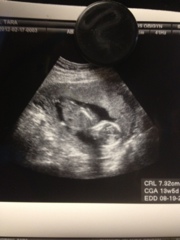

Baby is looking great, he or she was moving around like crazy on the screen so the photo is not the best ;) but arms were going and legs moving.

I have another appt in march and then a few days later we will be going in to find out the sex ;)

Very exciting